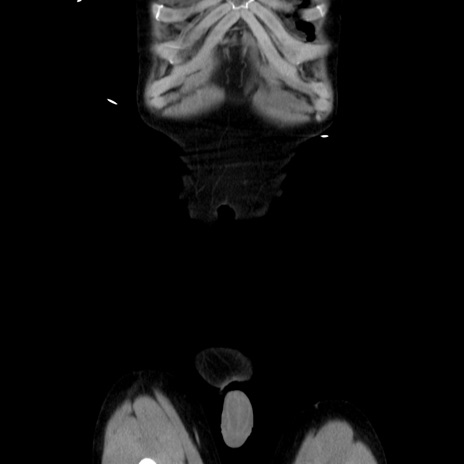

症例37(冠状断像)

【症例】40歳代 男性

【主訴】腹痛

【現病歴】4時間ほど前に電車に乗車中に臍部上より腹痛出現。徐々に増悪し起立困難となり、救急外来受診。生ものは数日食べていない。今朝お雑煮を食べた。

【身体所見】BT 36.8℃、BP 117/84mmHg、HR 91/min、SpO2 97%、苦悶様、腹部:臍上部広範囲圧痛あり、反跳痛±

【データ】WBC 8100、CRP 0.03